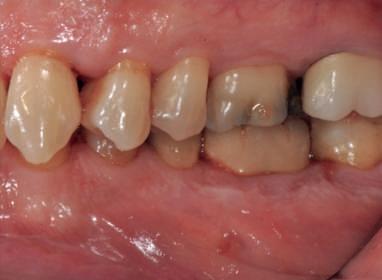

Examinarea parodontală a relevat sângerări generalizate la sondare și adâncimi de sondare de până la 9 mm la molarii maxilari și mandibulari, cu multiple furcații implicate la fiecare molar (fig. 2-7). Prezenta mobilitate multiplă de clasa I la dinții posteriori și de clasa II la dinții nr. 16 și 21 (molarul prim maxilar drept și incisivul central maxilar stâng).

Parodontologul a decis să evalueze dintele nr. 16 în privința PRS, deoarece acesta era molarul cel mai afectat parodontal care urma să fie tratat și menținut pe arcadă (fig. 2 și fig. 8). Acest dinte (molarul prim maxilar drept = scor 1) prezenta adâncimi de sondare de 7 mm (scor 1); trei invazii totale de furcație (scor 3) (mezial [furcație de grad II], vestibular [furcație de grad I] și distal [furcație de grad II]); și mobilitate de clasa II (scor 2). Valoarea totală a PRS pentru dintele 16 a fost de 8, reprezentând un prognostic „rezervat”. Pe baza acestui scor, probabilitatea de a nu pierde niciun dinte din cauza bolii parodontale timp de 15 ani a fost de 81%, iar pentru 30 de ani probabilitatea a fost de doar 56% (fig. 9).

2-4. Imagini înainte de tratament: lateral dreapta (fig. 2), frontal (fig. 3) și lateral stânga (fig. 4). Notă: Molarul prim maxilar drept (dintele 16) (fig. 2) ar fi identificat ca fiind molarul cel mai afectat parodontal care era planificat să fie menținut.